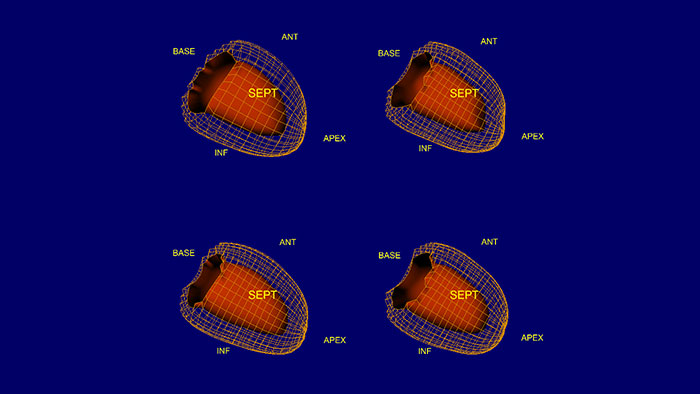

NM Corridor4DM 2018*

SPECT and PET cardiovascular quantification, review, and reporting

Designed for advanced cardiovascular quantification and image display, and includes intelligent workflow and quality assurance measures for increased confidence. Quantifies myocardial perfusion, function, and viability using multiple review screens, with integrated reporting through customizable templates.

Benefits

- Quantifies, displays, and provides reporting for SPECT and PET myocardial perfusion and function, PET FDG metabolism, and SPECT blood pool studies in a single, configurable application.

- Provides tools to generate and review DICOM static and multi-frame secondary screen captures.

- Configurable for different workflows, protocols, and preferences.

- LV surface estimation and quantification.

* Corridor4DM is a registered trademark of Invia, LLC.